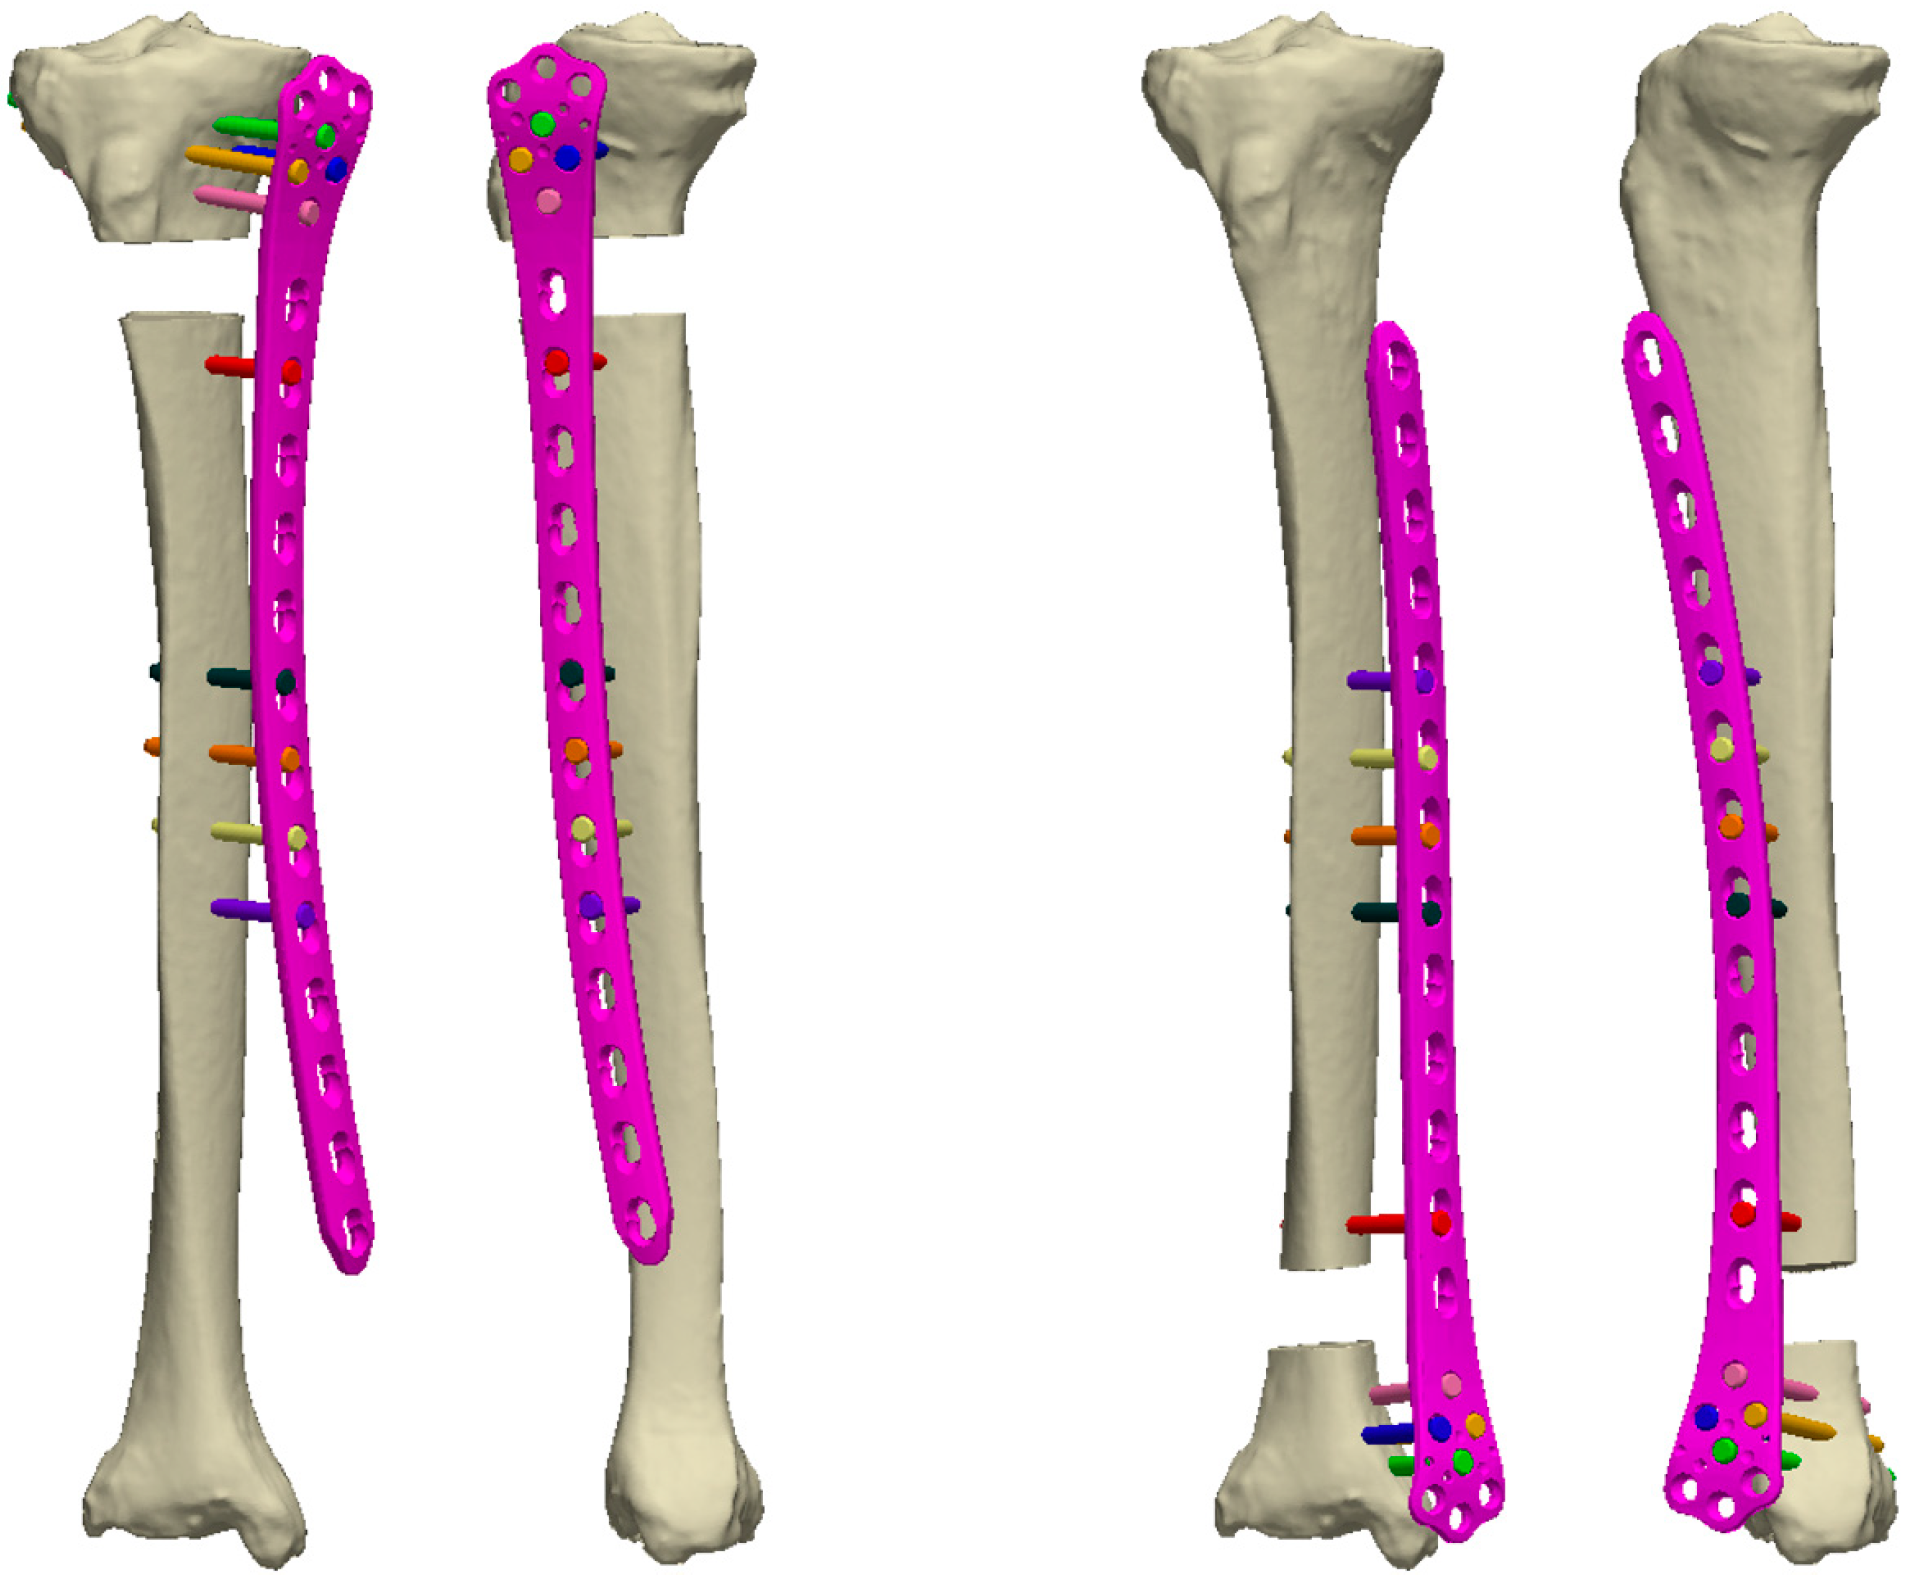

2.2.4. Virtual Biomechanical Analysis of Externalized Locked Plating